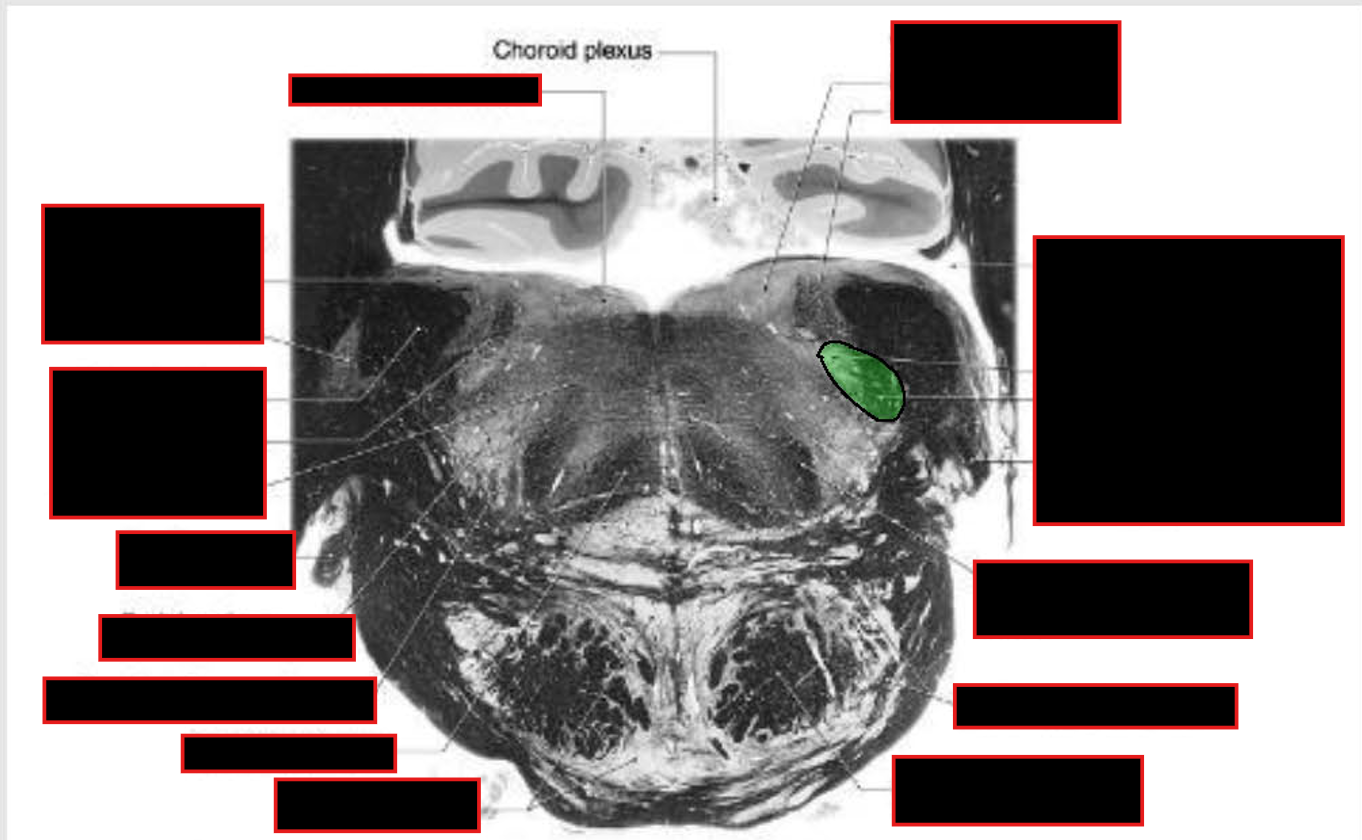

location of major tracts in the Caudal Pons:

CST/corticonuclear (bulbar) run through the substance of the basilar pons

Medial Lemniscus:

still in the midline

begins to turn → somatotopy shifts → leg areas = more lateral

anterolateral system

still in lateral position w/in pontine tegmentum,

@ anterolateral edge w/ formation of middle cerebellar peduncle.

Rubrospinal Tract:

Dorsal to ALS

Reticulospinals and vestibulospinals

still being formed in this area, so they are not clear.

spinal nucleus and tract of CN V

still present as pars oralis

just dorsal to the exit of the facial nerve.

MLF and tectospinal (tectobulbospinal ) tracts

dorsal position near the midline.

will now carry motor information for eye movements.

Other Ascending/Descending → displaced into the pontine tegmentum